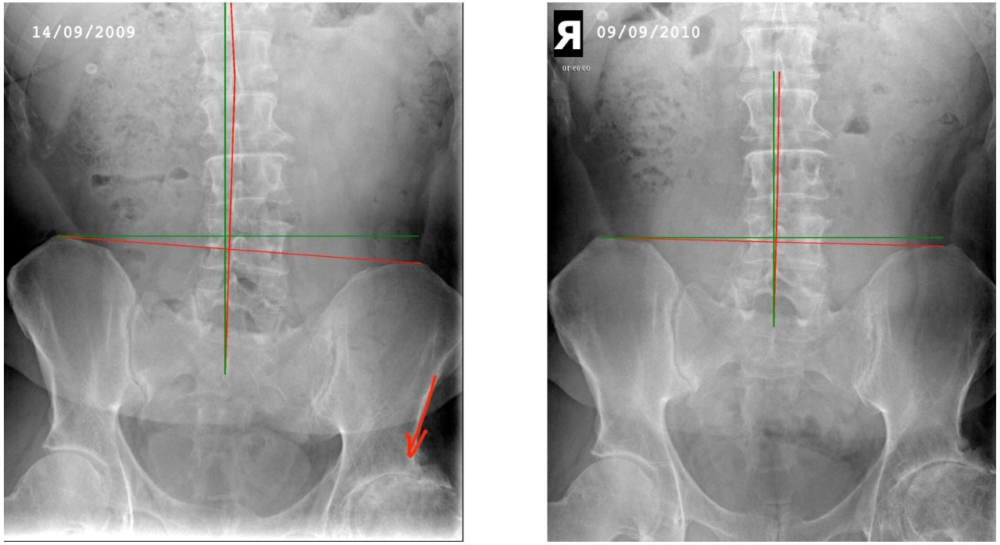

Is It Possible To Reverse Osteoarthritis?

Animal experiments support the hypothesis that immobilisation, for whatever reason, is one of the pathogenic factors in musculo-skeletal degeneration (this is commonly called ageing).